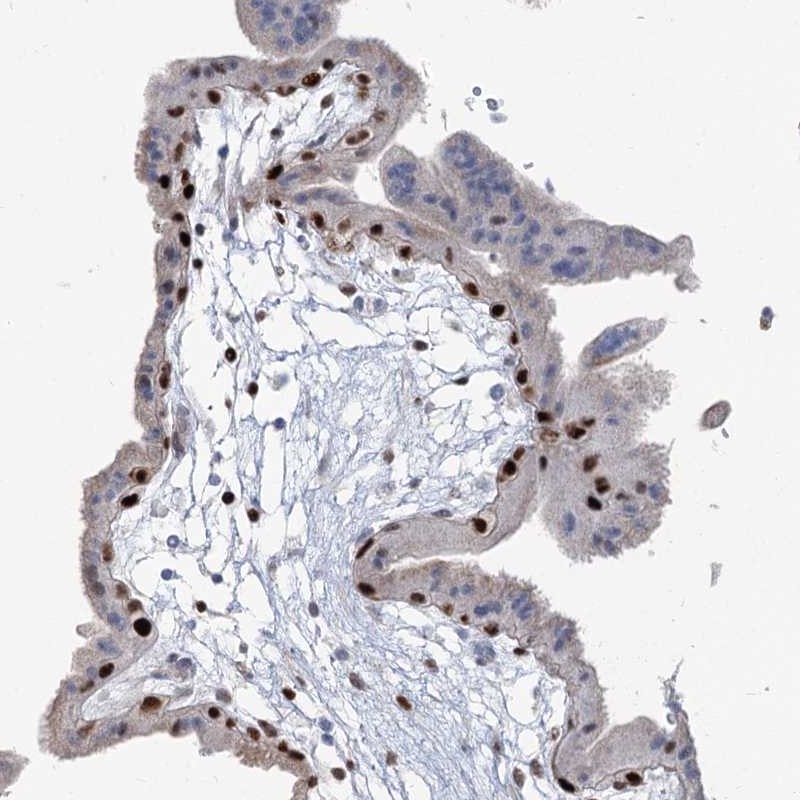

Immunohistochemical staining of human placenta shows strong nuclear positivity in trophoblastic cells.